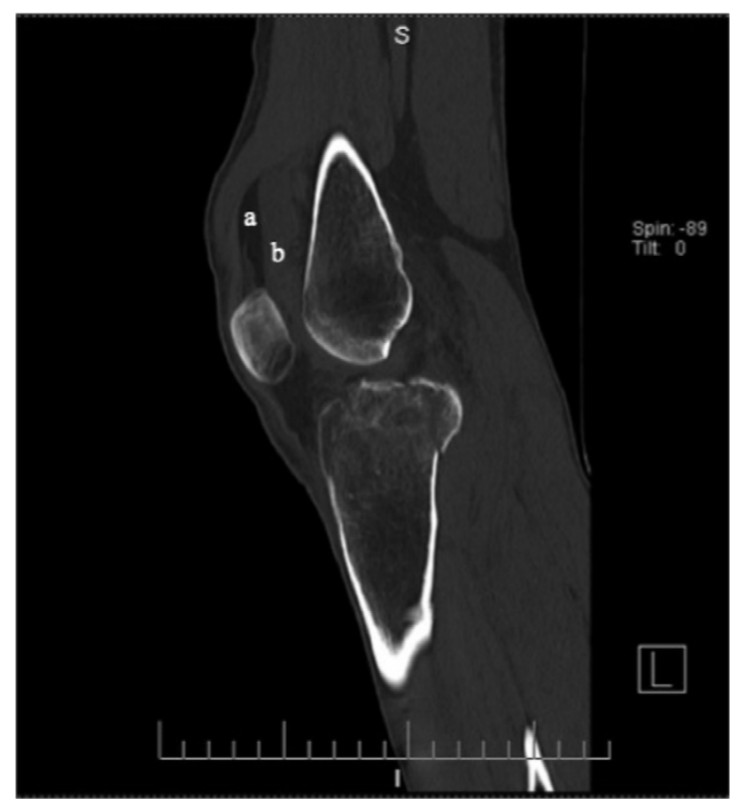

病例7 一例10岁患者肘关节外伤,侧位可见明显关节积脂血症。